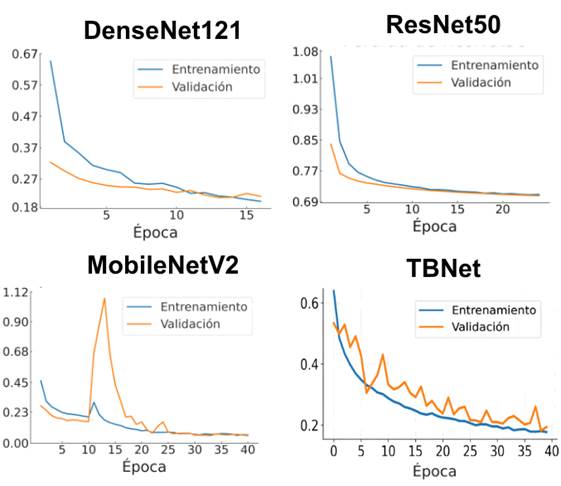

En la Figura 8 se evidencia diferencias claras en la estabilidad de las curvas de pérdida entre los modelos evaluados. DenseNet121 muestra la trayectoria más consistente, con una disminución progresiva y curvas de entrenamiento y validación muy próximas, lo que refleja un proceso de aprendizaje estable y sin fluctuaciones relevantes. ResNet50 presenta un patrón descendente aceptable, aunque con una convergencia más lenta. Por el contrario, MobileNetV2 y TBNet exhiben mayor variabilidad: MobileNetV2 presenta un pico abrupto de pérdida en validación, mientras que TBNet muestra oscilaciones repetidas a lo largo de las primeras épocas antes de estabilizarse. Estas fluctuaciones indican que, en términos puramente visuales.

Figura 8. Curva de pérdida por época de los modelos evaluados.

Elaboración: Los autores.

Si bien DenseNet121 mostró una mayor estabilidad durante el entrenamiento, reflejada en curvas de pérdida y precisión más uniformes, los resultados cuantitativos demuestran que la estabilidad visual del aprendizaje no siempre se traduce en un mejor rendimiento clínico. En este sentido, TBNet logró maximizar métricas críticas como accuracy, precisión y F1-Score, además de minimizar los falsos negativos, indicador clave en escenarios diagnósticos. Esta observación es consistente con estudios recientes que advierten que, en aplicaciones médicas, la priorización de métricas clínicas debe prevalecer sobre indicadores computacionales, ya que el impacto de un falso negativo puede comprometer el tratamiento oportuno del paciente (Rahman et al., 2020; Sánchez Figueroa et al., 2024).

Aunque DenseNet121 presentó la curva de pérdida más estable y un proceso de aprendizaje visualmente más consistente, los resultados cuantitativos mostraron que la estabilidad gráfica no siempre se traduce en el mejor desempeño final. En este estudio, TBNet demostró ser el modelo más eficiente para la detección de tuberculosis, aun cuando su curva de pérdida exhibió oscilaciones notables durante las primeras épocas. Estas variaciones no afectaron su capacidad discriminativa y el modelo logró converger adecuadamente y produjo las métricas más altas en precisión, accuracy y F1-Score.